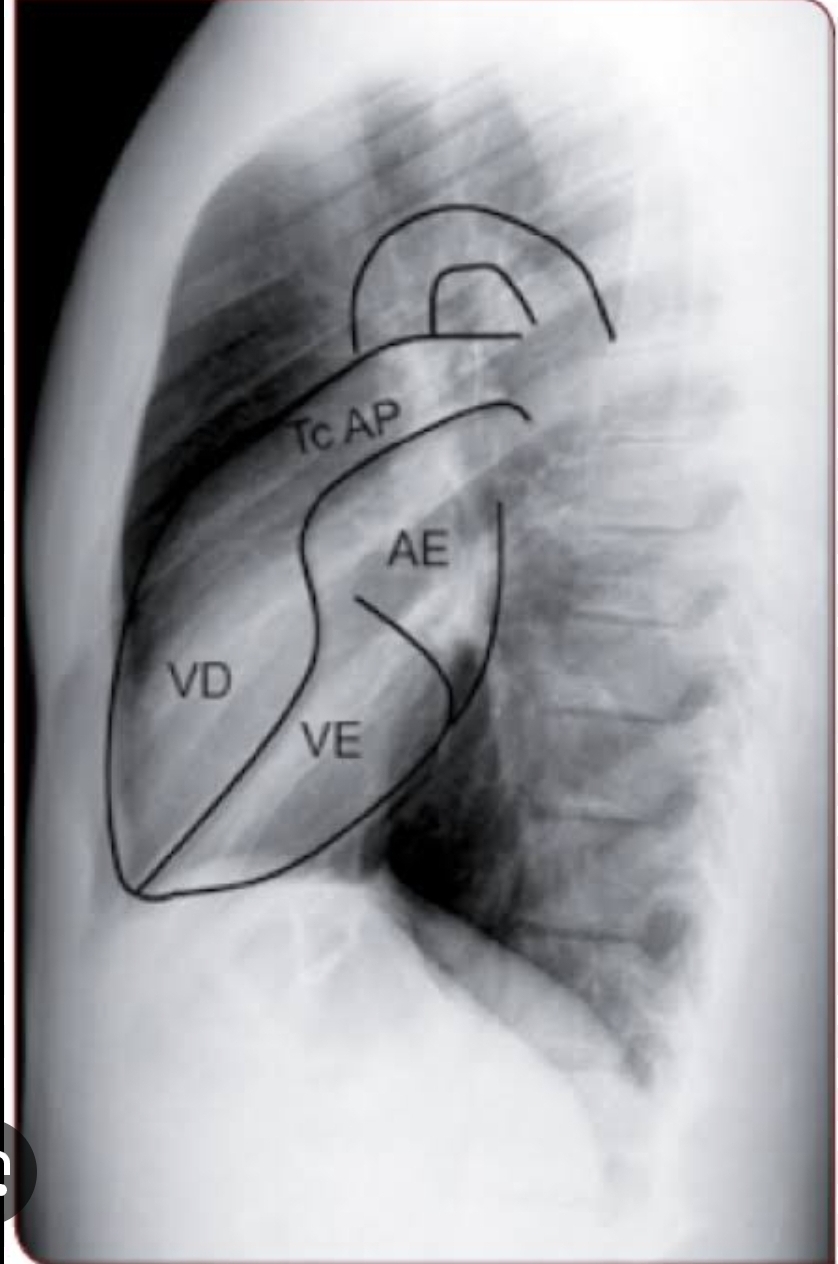

Q

Anatomia cardíaca em perfil?

A